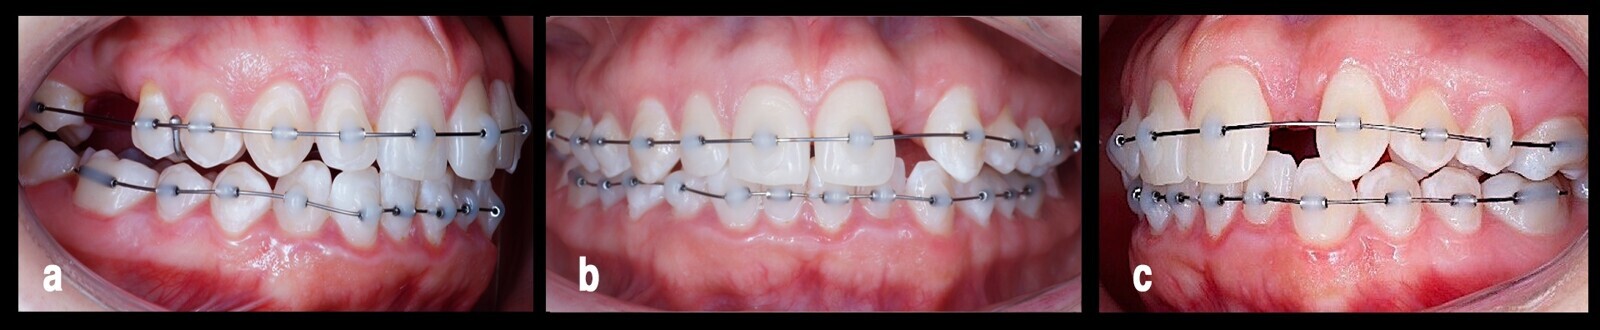

Se decidió iniciar el tratamiento en el maxilar superior realizando mecánicas seccionadas con el fin de evitar las fuerzas indeseadas reactivas en los dientes que presentaban acortamiento radicular, sobre todo en los incisivos centrales superiores5. Se diseñó un arco seccional con alambre calibre 0.016 (Special-Plus-Grade A.J. Wilcock), basado en la acción de un cantiléver en ortodoncia6 (Fig. 3).

Figura 3. Tres ángulos del arco cantiléver seccional de alambre (a, b, c), que se diseñó para evitar fuerzas reactivas en los dientes con acortamiento radicular.